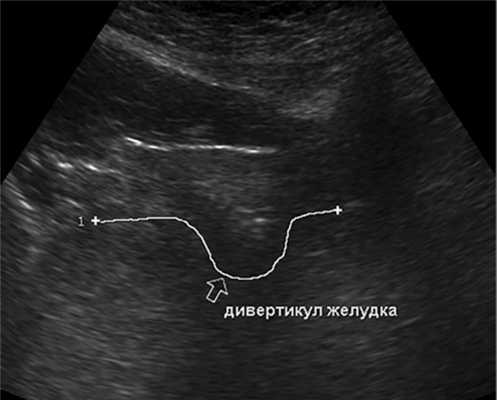

Из анамнеза известно, что при амбулаторном плановом обследовании в другом медицинском учреждении в феврале 2019 г. при УЗИ брюшной полости выявлено объемное образование в области тела поджелудочной железы. С целью уточнения диагноза выполнена МРТ органов брюшной полости, патологических изменений не выявлено. Однако пациентку по-прежнему беспокоили вышеописанные симптомы. При обращении в институт выполнено УЗИ брюшной полости, при котором в проекции перехода тела поджелудочной железы в хвост и нижней стенкой желудка лоцировалось объемное образование сниженной эхогенности 2,2×1,7 см, при цветовом допплеровском картировании кровоток достоверно не регистрировался. При наполнении желудка водой визуализировали дивертикул стенки желудка с жидкостным содержимым, наибольший размер около 3,2 см. Заключение: эхопризнаки дивертикула стенки желудка (рис. 1).

Рис. 1. Дивертикул желудка при УЗИ органов брюшной полости (сонограмма).